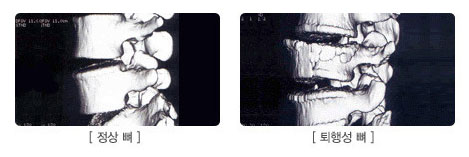

ÅðÇ༺ µð½ºÅ©´Â »À¿Í µð½ºÅ©¿¡ ³ëÈÇö»óÀÌ ÀϾ¸é¼ »ý±â´Â

ÁúȯÀÔ´Ï´Ù.

³ëȰ¡ ÁøÇàµÇ¸é¼ µð½ºÅ©³»ÀÇ ¼öºÐ°ú ¸»¶û¸»¶ûÇÑ »óŸ¦ À¯Áö½ÃÄÑÁÖ´Â ´Ü¹é ´Ù´ç·ù°¡ ¼Ò½ÇµÇ¾î

³³ÀÛÇÏ°Ô Âî±×·¯Áö°Ô µÇ¾î ÅëÁõÀÌ ¹ß»ýµÇ±âµµ Çϰí ôÃß Ç¥¸é¿¡ »À Á¶Á÷ÀÌ °¡½Ãó·³ ÀÚ¶ó³ª

ÅðÇàÈ µÇ¾î ¾ã¾ÆÁø µð½ºÅ©¿Í ÇÔ²² ½Å°æÀ» ÀÚ±ØÇÏ¿© ÁÖÀ§¿¡ ¿°ÁõÀ» ÀÏÀ¸Å°°í ÅëÁõÀ» À¯¹ßÇϴµ¥

À̸¦ ÅðÇ༺ Ãß°£ÆÇ º¯¼ºÁúȯÀ̶ó ÇÕ´Ï´Ù. |